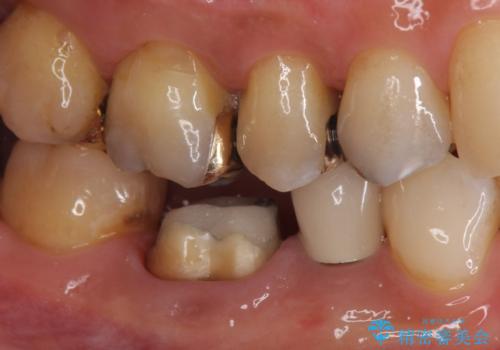

- 口を開けたときに下の歯の銀歯が目立つから白くしたいとのことで来院されました。

根管治療はご希望されなかったため、被せ物のみをやり替えていきます。